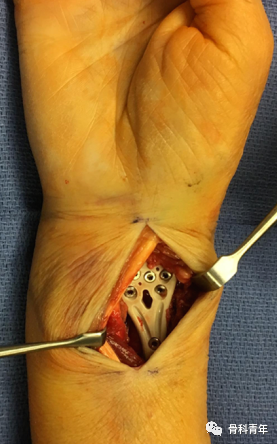

掌侧锁定加压接骨板(Volar locking compression plate,LCP)内固定是桡骨远端骨折治疗的金标准,但LCP并非对所有桡骨远端骨折均适用,如桡骨极远端骨折、背侧缘骨折、掌侧die-punch骨折等;同时,LCP钢板也具有一定的并发症发生率,包括旋前方肌损伤、骨折血运破坏、掌侧软组织激惹、背侧肌腱磨损等,同时对严重骨质疏松患者存在较高的内固定失效风险。

髓内钉技术广泛应用于长骨骨干骨折,闭合或有限切开复位有效降低医源性因素对血运的破坏,并具有良好的轴心固定生物学优势。桡骨远端髓内钉出现较晚,该技术适用于完全关节外骨折及简单的关节内骨折,对关节内粉碎骨折并不适用。

桡骨远端骨折髓内钉固定的前提是闭合复位效果满意,克氏针临时固定后,通过桡骨茎突开口,自腕背侧第1/2间室间隙进入。该技术存在潜在的损伤包括桡神经分支损伤,螺钉穿入下尺桡关节或桡腕关节等。